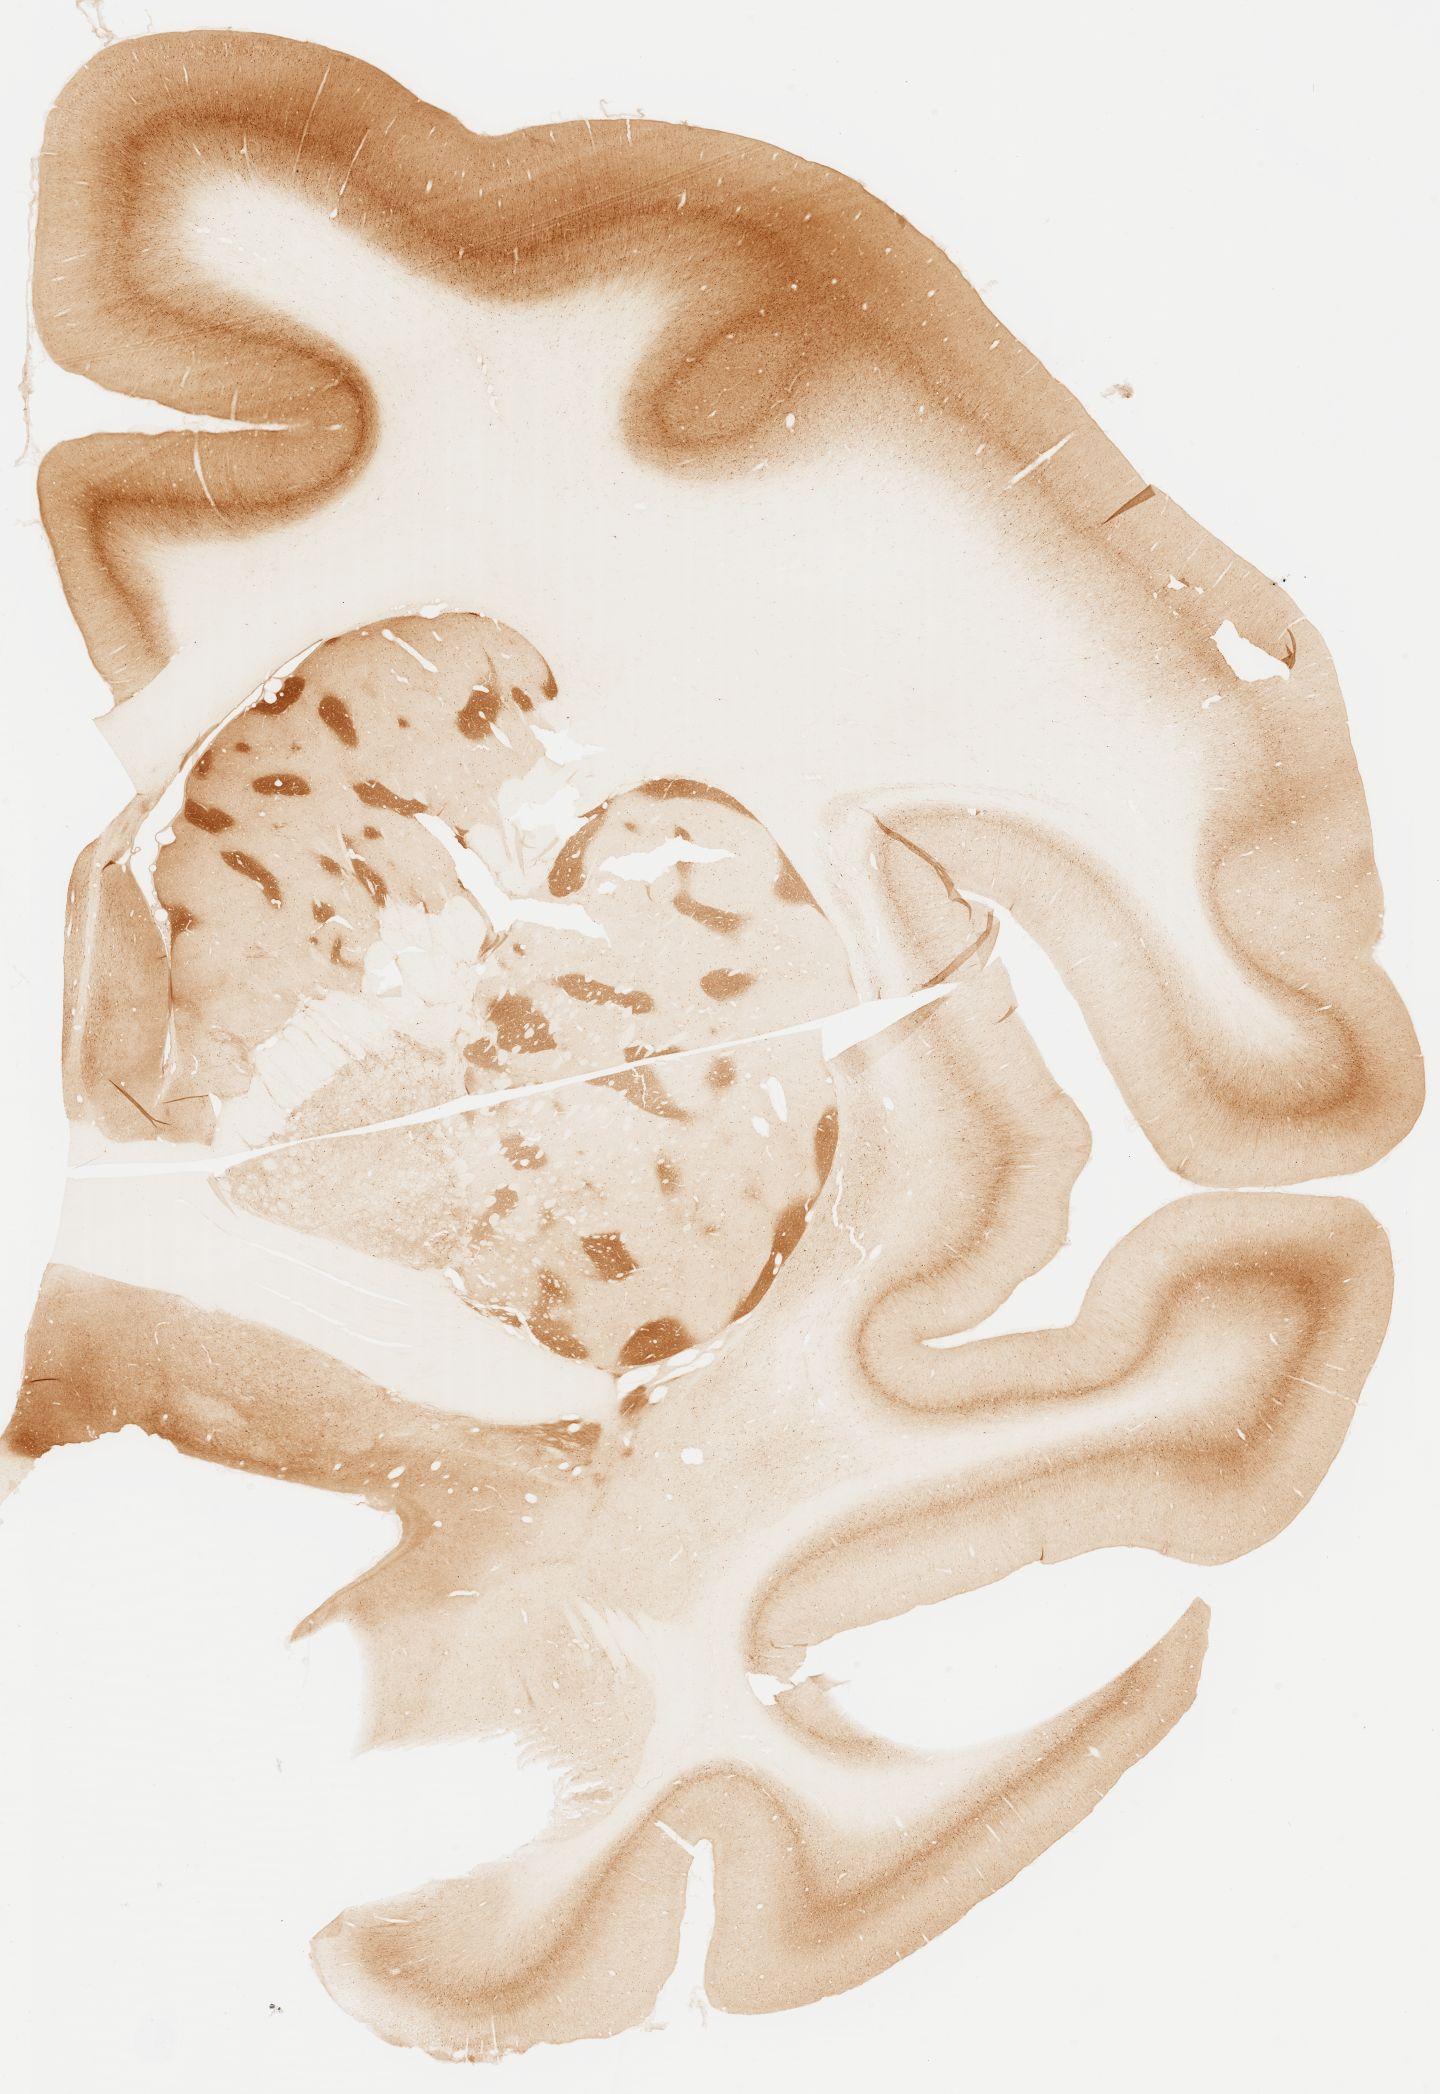

Datasets -> Macaca Fascicularis -> KChIP1, (Potassium Voltage-Gated Channel-Interacting Protein 1), coronal, immuno, Whole-Brain, adult

[ Metadata ]   ·   Source: Edward G. Jones

Displaying Sections 41 thru 80 of 92 Sections for this Dataset